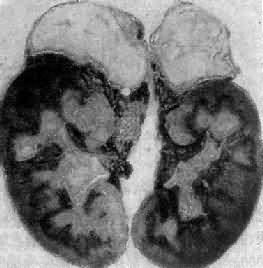

引起本病的病因主要有双侧肾上腺结核(图15-15)和特发性肾上腺萎缩,偶尔也可因转移癌引起。特发性肾上腺萎缩(idiopathic adrenal atrophy)是自家免疫性炎症,故又称自家免疫性肾上腺炎(autoimmue adrenalitis),多见于青年,女性显著多于男性。病人血中常有抗肾上腺皮质细胞线粒体微粒体抗体,常与其他自家免疫性疾病合并。双侧肾上腺高度萎缩,共重2.5g以下;皮质菲薄,镜下除皮质萎缩外,有大量淋巴细胞浆细胞浸润

双侧肾上腺结核

图15-15 双侧肾上腺结核